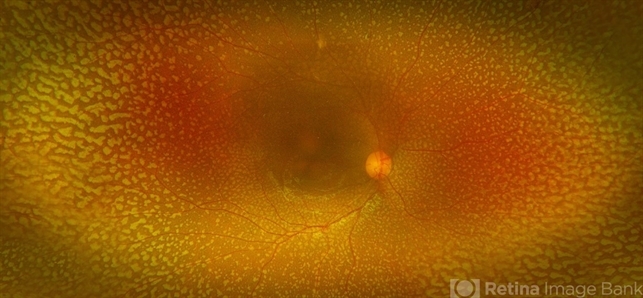

- fleck retinopathy

- Flecks over the entire retinal mid-periphery and periphery of a 12-year-old male with no visual complaints.